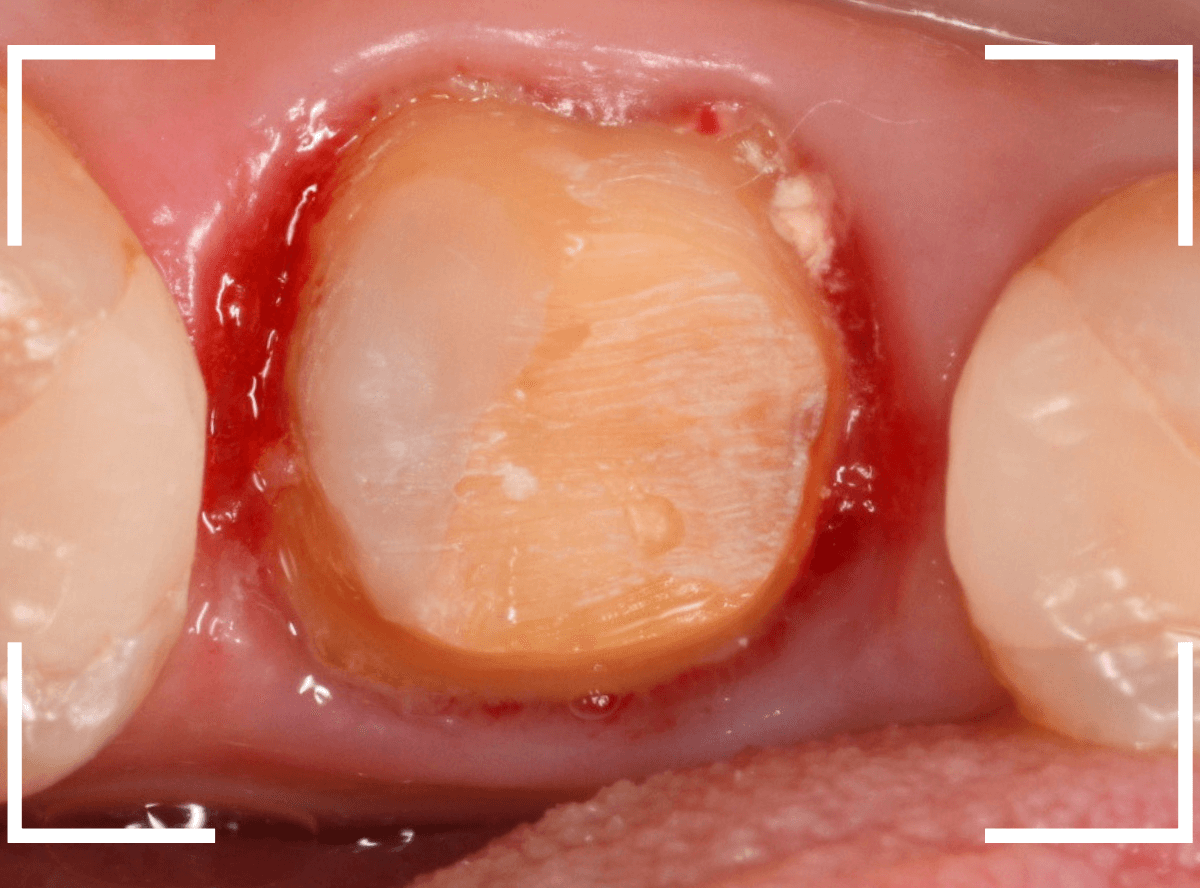

患者さんに状況を説明し、歯の周りの歯肉を麻酔をして電気メスでトリミングします。

このように歯の際が歯肉からしっかり出てる状況で製作しないと、さし歯はしっかりお口の中で安定しません。

この状態で新しい土台(ファイバー・コア)の型を取ります。